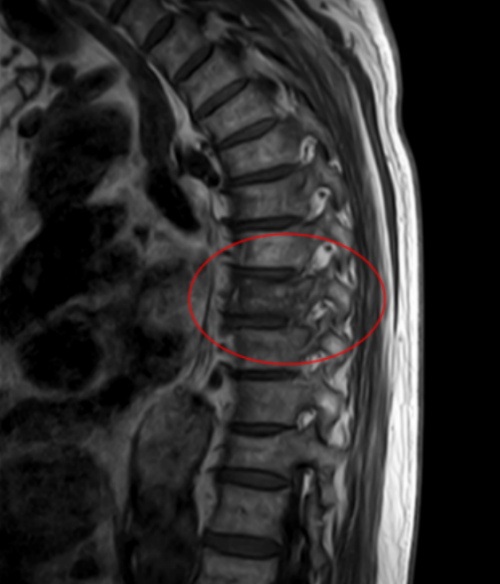

核磁共振显示王大爷T8胸椎压缩性骨折

据家属回忆,早在几年前,社区医生就提醒过老人,体检结果显示他有骨质疏松,需要重视。但老人自认为身体很健康,没太重视,直到这次因为举杠铃导致T8胸椎压缩性骨折入院,老人才认识到骨质疏松的危害。

长沙市中心医院脊柱外科二区主任曾浩介绍,王武成老人骨折的原因,并非简单的动作失误造成的,其根本在于老年性骨质疏松。骨骼如同建筑的钢筋,随着年龄增长,尤其是老年人,骨量自然流失,骨骼退化,导致骨密度下降、骨骼脆性增加。此时,骨骼承受外力的能力显著降低。像打沙袋瞬间的冲击力、举杠铃时脊柱承受的垂直压力,对于已骨质疏松的脊柱来说,可能已超出了安全负荷,从而引发骨折。尽管老人一直坚持健身,看上去身体很“硬朗”,但其骨骼的内部结构,已悄然进入了需要特别呵护的“脆弱期”。此外,还有一个不容忽视的原因:王大爷体重高达160斤,大基数使得骨骼同样长期受压,加剧了脊柱负担,更易致骨折。